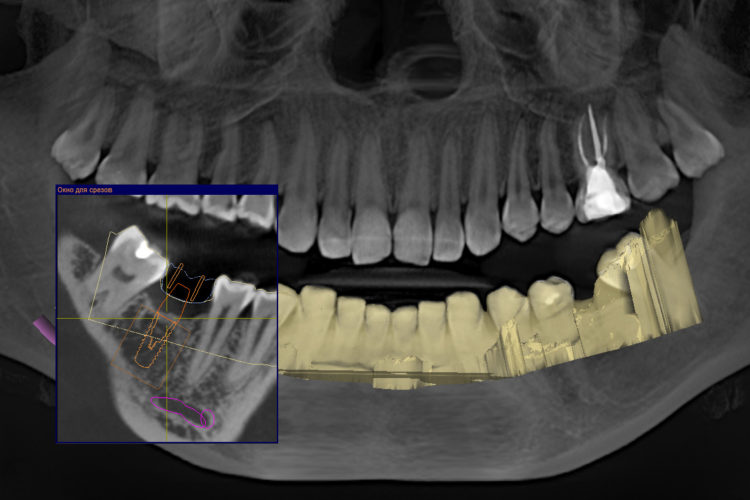

Клинический кейс имплантации

Все этапы: от компьютерной томограммы до установки коронки на имплант.

Установленный имплант: 4.5 мм на 11.5 мм

Коронка на имплант: дисиликат лития, винтовая фиксация, изготовлена в клинике за 3 часа.

Абатмент: индивидуальный титановый.

Длительность имплантации: 1.5 часа.

Промежуток от импланта до коронки: 3 месяца.

Заключение: проведена установка импланта с одновременной пластикой десны и формированием межзубных сосочков. В имплант установлен формирователь десны. Рана ушита. Швы необходимо снять через 10-14 дней. Даны рекомендации в послеоперационный период.

Установка коронки на имплант запланирована через 3 месяца.

1. Предварительно пациенту проводится компьютерная томография челюстей. Это трехмерное изображение челюстей на котором доктор оценивает тип кости, расположение важных анатомических образований (например, на нижней челюсти - это нижнечелюстной канал, в котором проходит нижнечелюстной нерв; при неправильной подобранной длине импланта зуба возможно повреждение нерва и нарушение чувствительности половины нижней челюсти и языка).

В специальной программе мы подбираем оптимальный размер импланта: его длину и диаметр. Диаметр импланта подбирается с учетом ширины альвеолярного отростка (участка кости, куда будет установлен имплант). После анализа полученных данных мы предлагаем пациенту возможные варианты системы имплантов различной стоимости, с описанием их преимуществ и недостатков. Процент приживаемости достаточно высокий у всех систем, однако у имплантов Штрауман и Нобель этот показатель самый высокий, а вероятность отторжения наиболее низкая.

2. Виртуальная установка выбранного импланта в челюсти. В программе планирования имплантации мы выбираем в каталоге необходимого производителя имплантов, тип импланта, а также его длину и диаметр. Затем располагаем его в костной ткани челюсти и повторно проверяем расположение относительно рядом стоящих зубов и анатомических образований. В сложных клинических ситуациях дополнительно проводится виртуальное протезирование. Например, при восстановлении зубов на беззубых челюстях - предварительное планирование будущего протеза очень важно и позволяет разместить импланты в челюсти таким образом, чтобы обеспечить равномерное распределение жевательного давления и высокий эстетический показатель.

Важно: чтобы поставить имплант зуба необходимо 3D изображение челюсти; планирование имплантации не проводится по двухмерным изображения (по обычному рентген снимку), так как они не позволяют оценить необходимые показатели: ширину и высоту костной ткани.